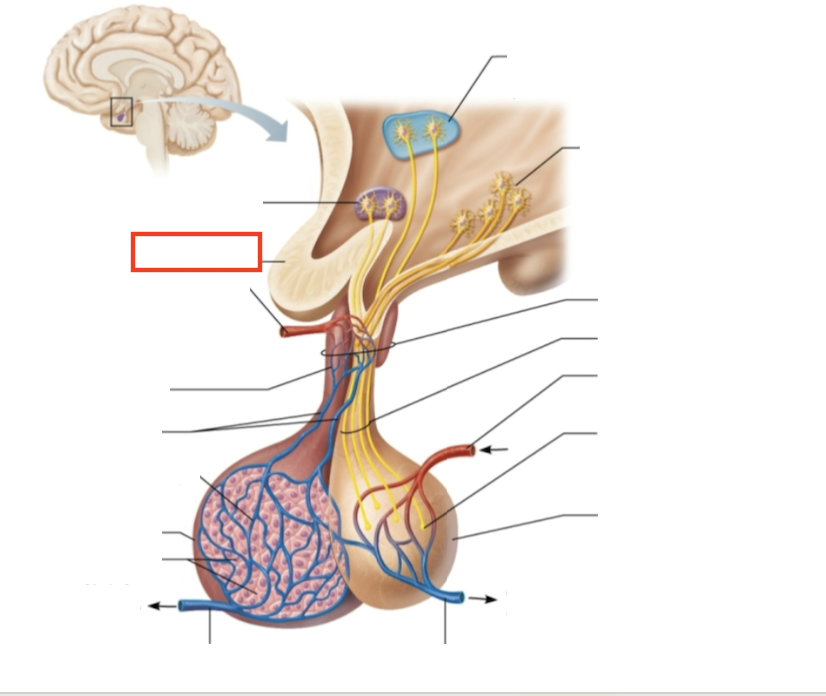

testes (male)

What structure is highlighted?

hypothalamic neurons in the paraventricular nuclei

What structure is highlighted?

neurons in the ventral hypothalamus

What structure is highlighted?

infundibulum (connecting stalk)

What structure is highlighted?

hypothalamic-hypophyseal tract

What structure is highlighted?

inferior hypophyseal artery

What structure is highlighted?

neurohypophysis (storage area for hypothalamic hormones)

What structure is highlighted?

posterior pituitary

What molecules are produced here?

oxytocin, ADH

What structure is highlighted?

venule

What structure is highlighted?

venule

What molecules are produced here?

TSH, FSH, LH, ACTH, GH, PRL

What structure is highlighted?

secretory cells of adenohypophysis

What structure is highlighted?

anterior pituitary

What structure is highlighted?

secondary capillary plexus

What structure is highlighted?

hypophyseal portal veins

What structure is highlighted?

primary capillary plexus

What structure is highlighted?

superior hypophyseal artery

What structure is highlighted?

superior hypophyseal artery

What structure is highlighted?

optic chiasma

What structure is highlighted?

hypothalamic neurons in the supraoptic nuclei

What are the target organs and effects of testosterone?

most cells of the body; promotes the maturation of the male reproductive organs, the development of secondary sex characteristics, sperm production, and sex drive

What hormone is produced by the testes?

testosterone

What stimulates testosterone production?

LH and FSH